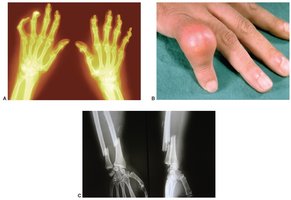

Common Disorders

Inflammatory: Osteoarthritis, gout

Infectious: Osteomyelitis

Porous bone: Osteoporosis

Fractures, developmental conditions (gigantism, dwarfism), tumors

Laboratory Tests

Calcium, phosphate, vitamin D, ALP

ANA, ESR, CBC

Bone marrow or synovial fluid cultures